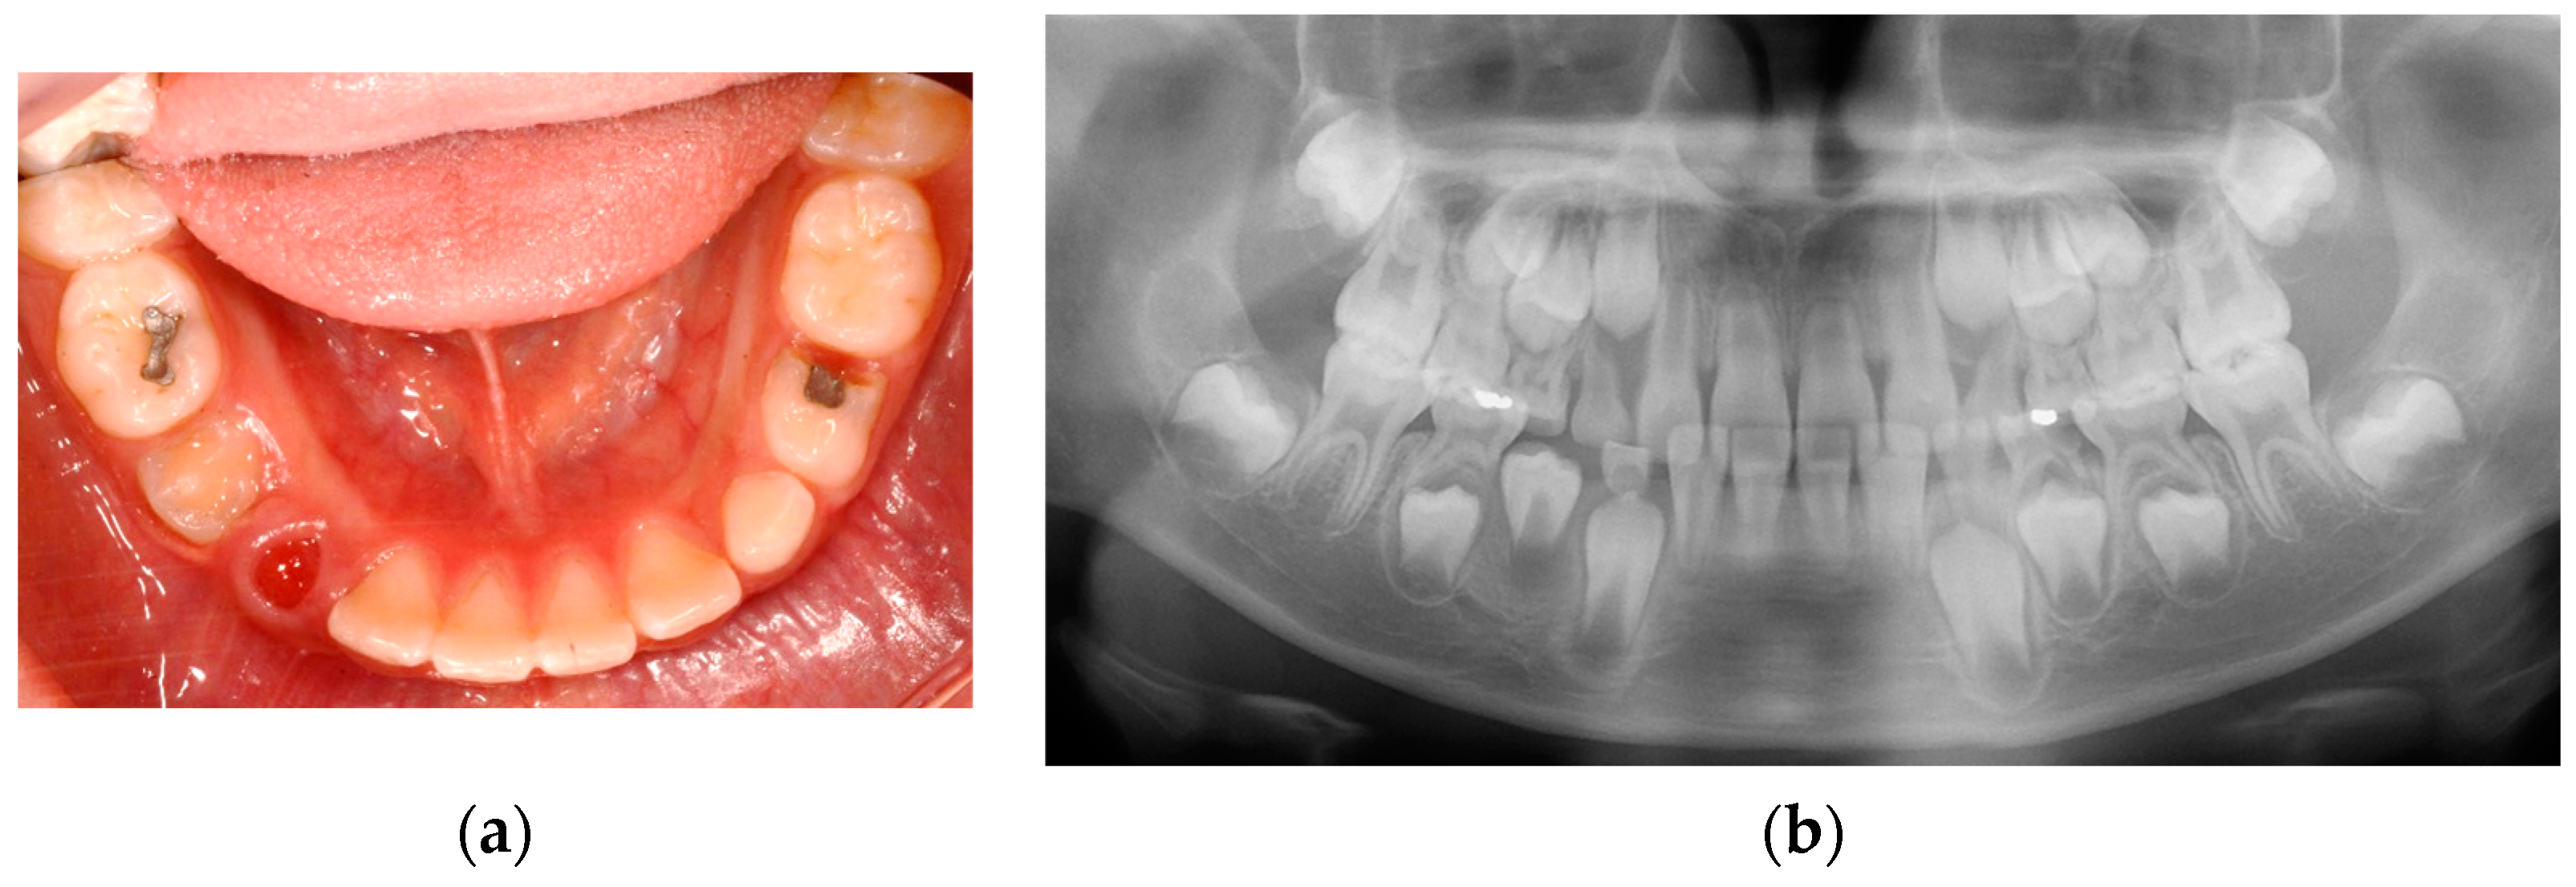

An 8-year-old boy visited the Department of Pediatric Dentistry of Kyung Hee University Dental Hospital with facial swelling on the right side of the mandible and pus discharge from the right mandibular primary first molar that had been previously treated at a local dental clinic. His medical history was unremarkable. His dental history was pulpectomy and restoration with a stainless-steel crown on the right mandibular primary first molar a year before at a local dental clinic. According to the guardian’s statement, there had been minor, painless swelling in the particular region with fluid discharge after the treatment. On dental examination, pus discharge via the right mandibular primary first molar’s disto-lingual sulcus was shown. He had poor oral hygiene and facial swelling on the right side of the mandible. Radiological examination showed a cystic lesion in the successive right mandibular first premolar region with buccal bone expansion and root resorption of the affected primary molar. In addition, a broken file was identified at the distal root tip of the affected primary molar (Figure 7).

Figure 7.

Initial visit: (a) panoramic radiograph; (b) cone-beam computed tomography; the cystic lesion around the successive right mandibular first premolar can be seen and the buccal bone swelling are observed; (c) periapical radiograph. A broken file is noted on the distal root tip of the affected primary molar (red arrow).

Under local anesthesia, the right mandibular primary first molar was extracted, marsupialization of the cyst associated with the successive permanent tooth was performed at the second visit, and the separated file was retrieved simultaneously. A removable space maintainer (RSM) with a tube was placed to facilitate the irrigation of the cystic lesion, and the patient’s caregiver was instructed to perform saline irrigation twice daily (Figure 8). Postoperatively, analgesics and antibiotics were prescribed for 3 days, and a 0.13% chlorhexidine mouth rinse was prescribed.

Figure 8.

The extraction of the right mandibular primary first molar and cyst marsupialization were performed: (a) intraoral photo after treatment; (b,c) removable space maintainer (RSM) with a tube; (d) intraoral photo with RSM.

Three days post-treatment, the patient had no complaints, and facial swelling had reduced. Three weeks post-treatment, the facial swelling had nearly subsided, and the RSM was eliminated. Two months post-treatment, the cystic lesion had reduced in size, and the occlusal surface of the mandibular right first premolar was visible intraorally (Figure 9).

Figure 9.

Two months after the marsupialization: (a) intraoral photo; (b) panoramic radiograph.

Four months post-treatment, the bone expansion was remarkably reduced, and dens evaginatus was identified on the premolar. The patient showed no clinical symptoms.